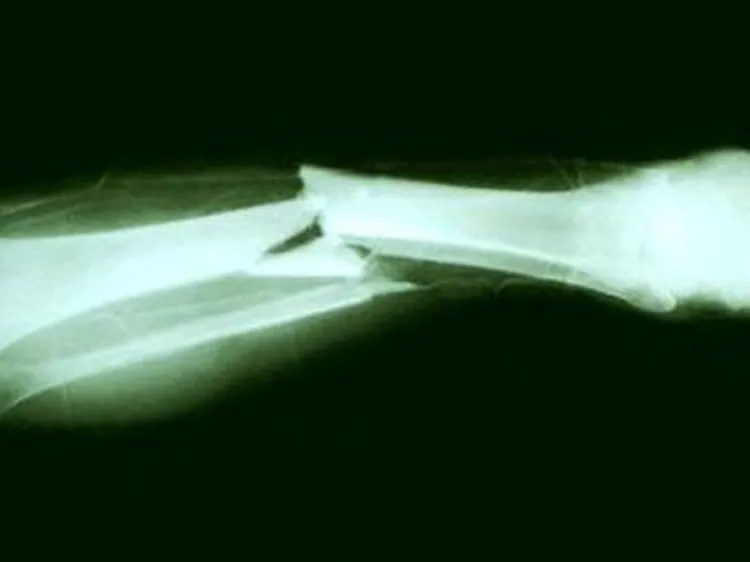

CIUDAD DE MÉXICO.- Todo por los likes y los views, es el lema de los los streamers.Esto lo sabe bien Sjokoladen, un streamer noruego que utiliza con frecuencia la plataforma Twitch.El hombre se rompió la pierna tras resbalar varios metros en una montaña cuando daba un paseo cerca de Oslo.Increíblemente pese a la dolorosa caída y la grave lesión, no dejó de grabar hasta que la ayuda llegó.En el hospital determinaron que había sufrido una fractura en dos huesos de la pierna y un desplazamiento de rótula de 4 milímetros. Y sí, como era de esperar compartió con sus seguidores fotos del hueso roto.